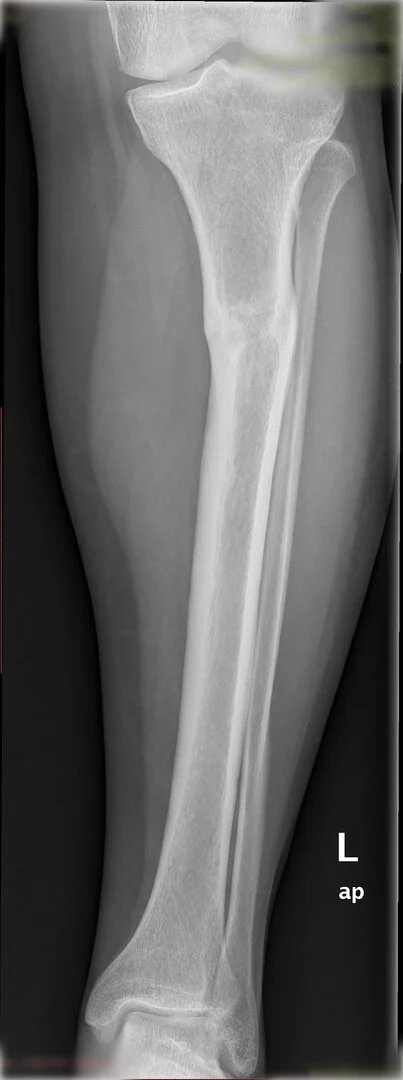

Deformite, bir kırık sonrası yanlış kaynama sonucunda olabileceği gibi doğumsal nedenlerden de olabilir.

Ameliyat öncesi deformitenin iyi analiz edilmesi, planlamanın ona göre yapılması gerekir. Deformite düzeltilmesi esnasında eğer kısalık var ise sıra ile iki problemin de aynı anda düzeltilmesi mümkündür.

Diğer bir yöntem akut olarak düzeltme yöntemidir. Bu yöntemde kemiğe uygulanılan tespit yöntemi plak-vida kombinasyonu olabileceği gibi bir intramedüller çivi de olabilir.

Hangi tespit yöntemini kullanacağınıza deformitenin yeri ve miktarına göre karar vermek gereklidir.

Görüntüleri büyütmek için üzerine tıklayınız.